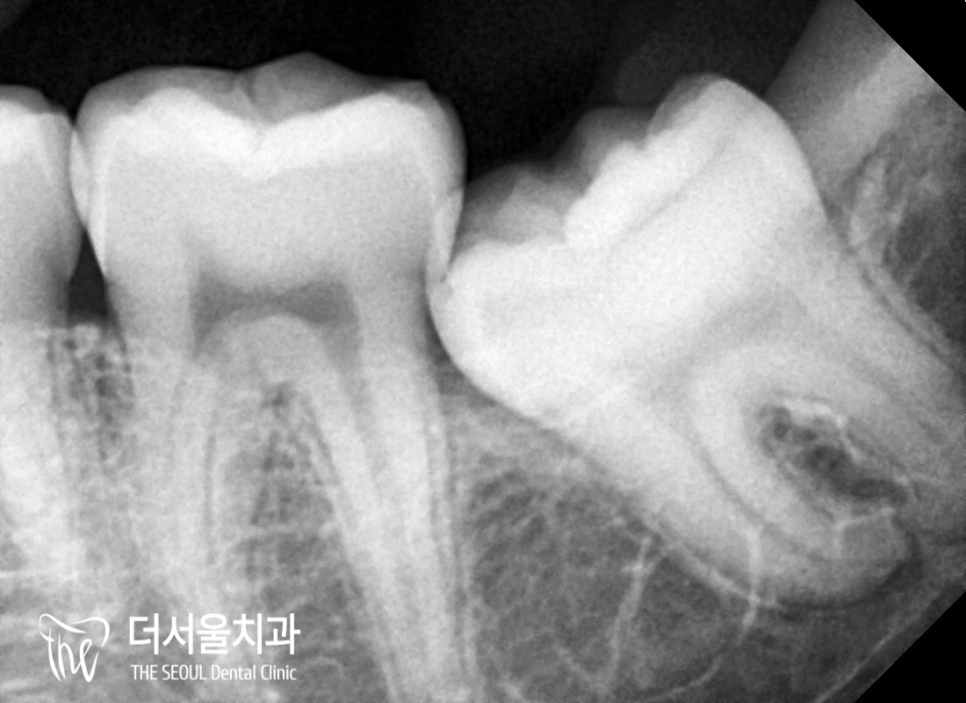

이분의 경우 뿌리가 뼈를 움켜지고 있는

얄미운 형태를 갖고 있었던 분이었는데요.

이런 경우에는 일부 뼈를 깎아내는 방식도

고려해 봐야 되기 때문에 정상 형태보다

훨씬 더 까다롭고 어려운 과정이 될 수밖에 없죠.